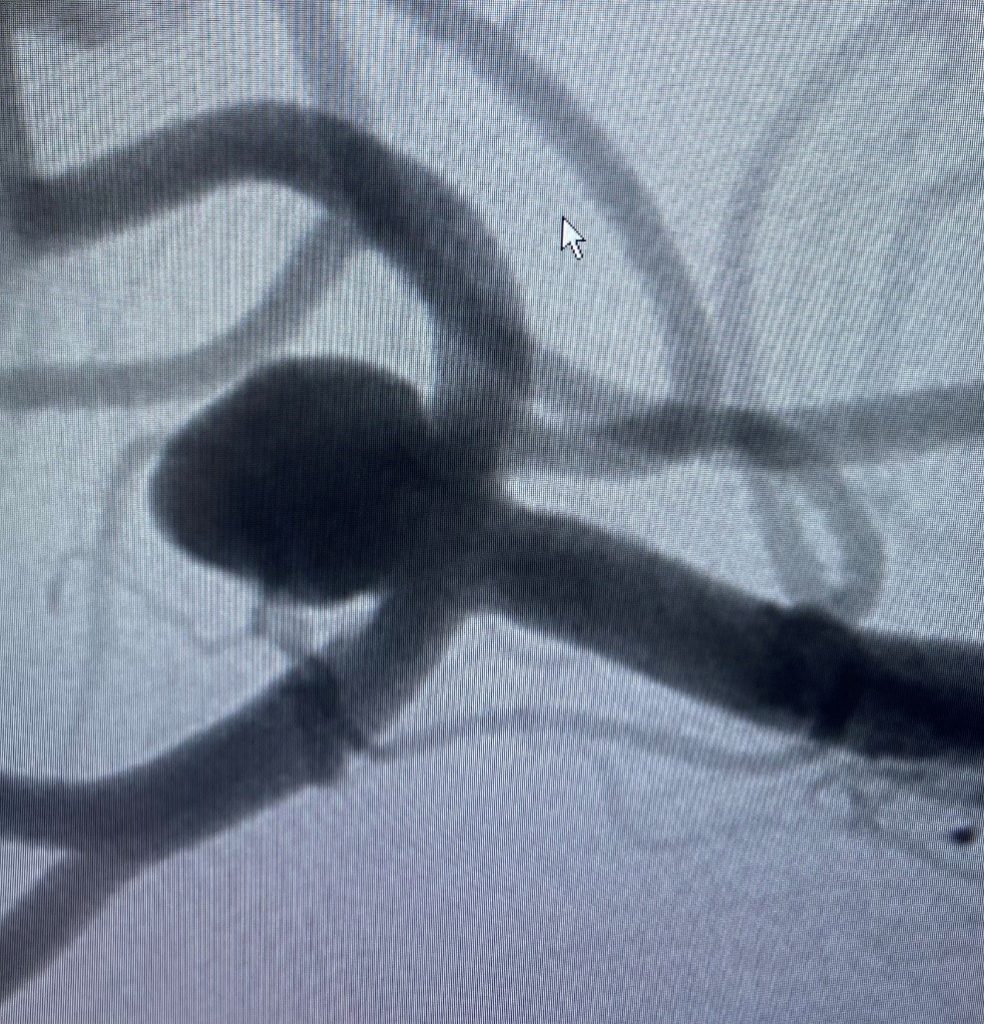

Right middle cerebral artery wide neck bifurcation aneurysm (red arrows). Dotted yellow line outline the aneurysm neck.